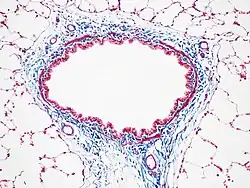

Masson's trichrome stain

Masson's trichrome is a three-colour staining procedure used in histology. The recipes emerged from Claude L. Pierre Masson's (1880–1959) original formulation have different specific applications, but all are suited for distinguishing cells from surrounding connective tissue.

Most recipes produce red keratin and muscle fibers, blue or green collagen and bone, light red or pink cytoplasm, and dark brown to black cell nuclei.

Another common variant is the Masson trichrome & Verhoeff stain, which combines the Masson trichrome stain and Verhoeff's stain.[2] This combination is useful for the examination of blood vessels; the Verhoeff stain highlights elastin (black) and allows one to easily differentiate small arteries (which typically have at least two elastic laminae) and veins (which have one elastic lamina).